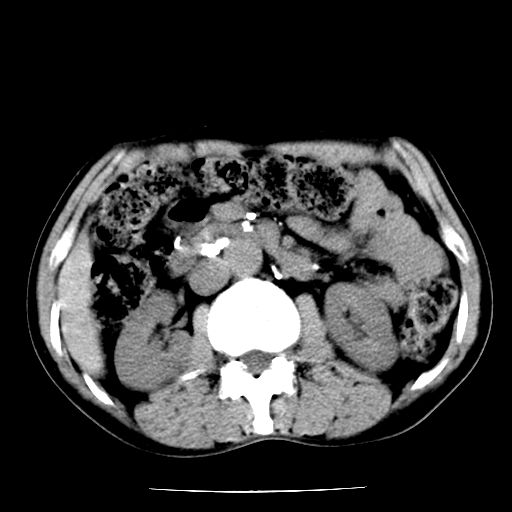

男,59岁,“结核性胸膜炎”30余年,胸部经常疼痛,多次x检查提示“肺部”炎症。腹部疼痛5日,b超提示:“肝内短管结石,余显示不清,建议进一步检查。”

两肺结核并右侧胸腔积液;脾脏、腹腔及腹膜后淋巴结结核[陈旧性];肝内胆管结石

胸部腹部都是结核(双肺。纵隔淋巴结,肝脏,脾脏,肠系膜)

两肺结核并右侧胸腔积液;脾脏、腹腔及腹膜后淋巴结结核[陈旧性];肝内胆管结石。直肠息肉?